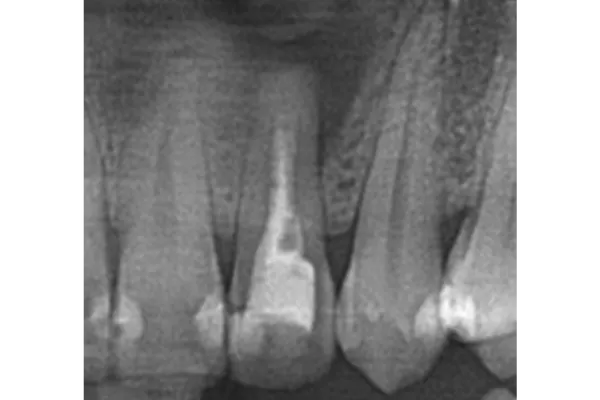

症例② 左上の歯をぶつけて他院で治療してもらったが膿みが治らない

Before

After

| 主訴 | 左上の歯をぶつけて他院で治療してもらったが膿みが治らない |

|---|---|

| 治療期間 | 4ヶ月 |

| 治療費 | 国民健康保険の範囲内 |

| 治療内容 | 根管治療・歯根端切除術・逆根幹充填(外科処置) |

| 治療のリスク | 根管治療中の炎症による痛み/外科処置後の腫れ・痛み |

▲治療のコメント

今回のケースでは、当院で再度根管治療を行いました。根尖の病変が大きく、再発を繰り返していたことより、嚢胞形成をしている可能性が高いと判断しました。そのことより、外科的な治療が必要になる可能性をお伝えした上で、経過観察を行っていました。3ヶ月後再発・排膿したので、予定通り歯根端切除と逆根幹充填を行いました。それからは再発することなく、1年経過のレントガン写真でも根尖病変の消失が確認できます。